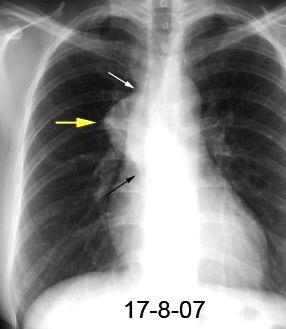

113. MASA MEDIASTÍNICA FOCAL

153. VENA CAVA SUPERIOR. SÍNDROME DE 155. VCS SÍNDROME. . TROMBOSIS